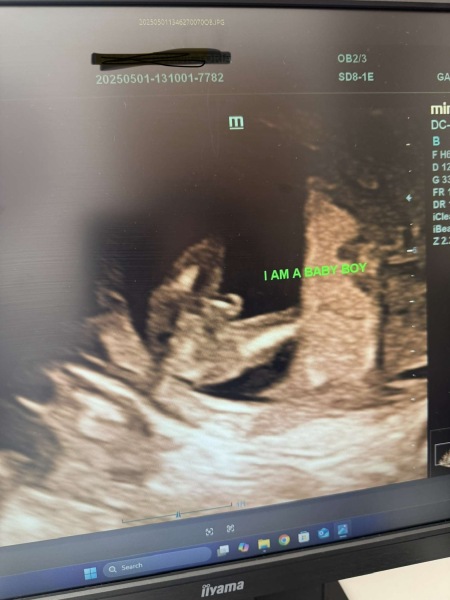

@RavensMom24 definitely a little boy!

RavensMom24 · 01/05/2025 15:09

Update - @emmatcc1 you were absolutely right - we’re having a boy!!😊💙 He wasn’t shy about showing us either! 😂🙈

We already have our daughter who’s 13 months so we will be one of each, approx 19 months apart.

Should be fun and games for a few years🤣 but we’re looking forward to it! lol Now to think of a name lol! x

Thank you! @Givemethesun and yeah it was a private scan and I’m 15 weeks exactly.